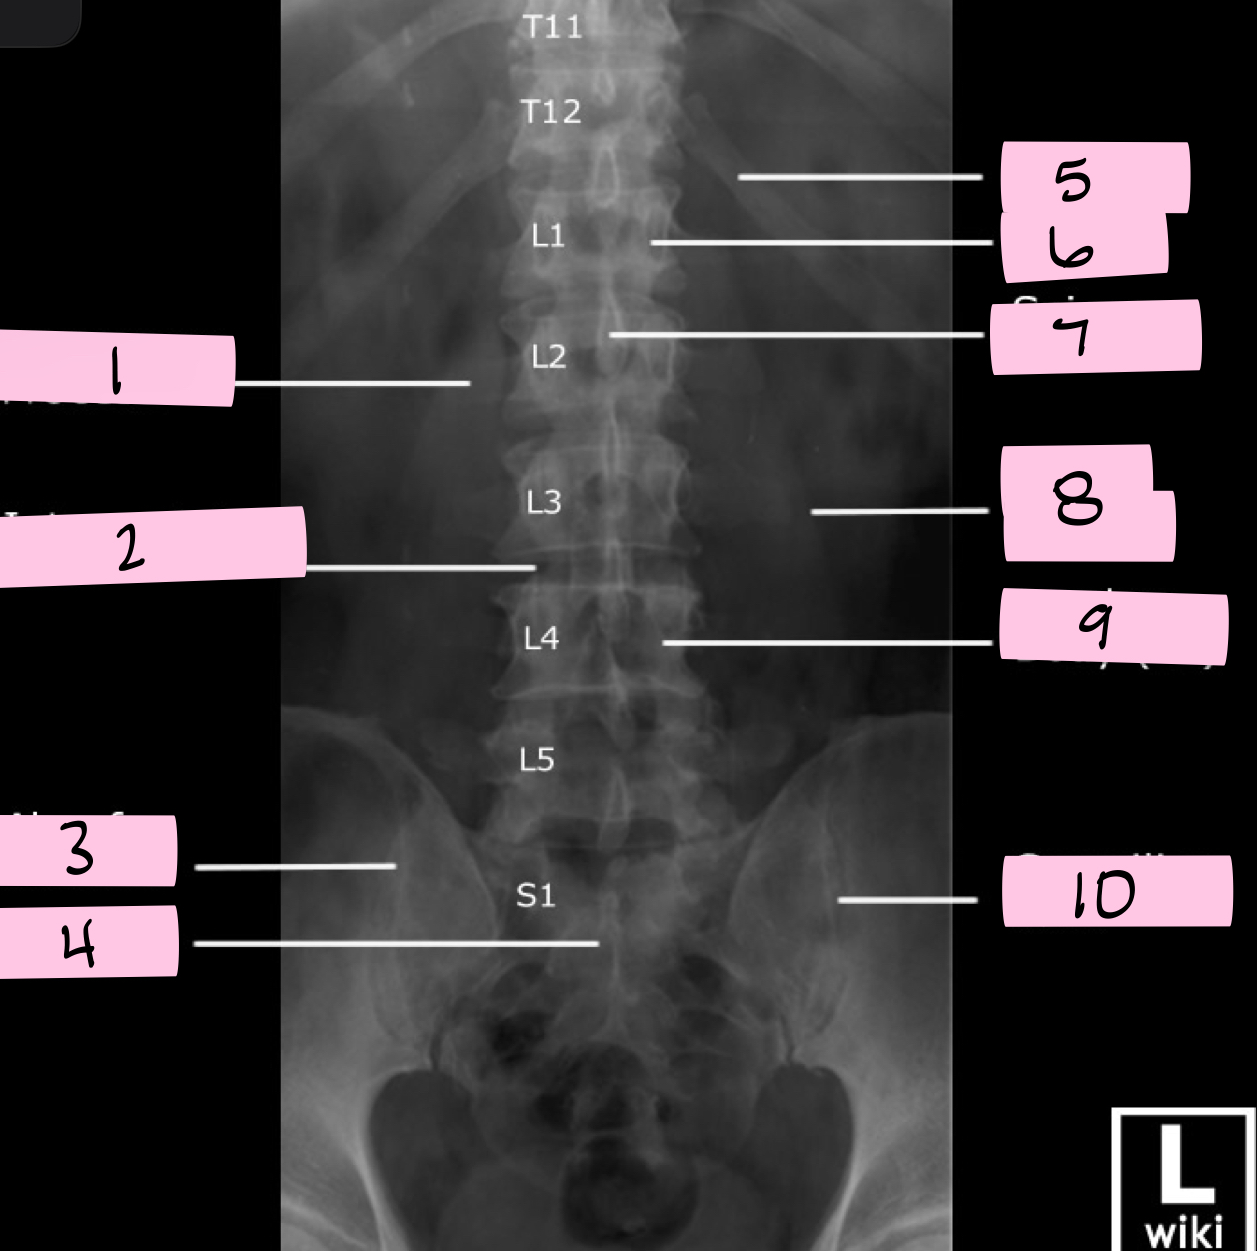

What is 1 pointing to?

Transverse process

What is 2 pointing to?

Intervertebral disk

What is 3 pointing to?

Ala of sacrum

What is 4 pointing to?

Sacrum

What is 5 pointing to?

12th Rib

What is 6 pointing to?

Pedicle

What is 7 pointing to?

Spinous process

What is 8 pointing to?

Psoas muscle

What is 9 pointing to?

Lumbar body (L4)

What is 10 pointing to?

Sacroiliac joint